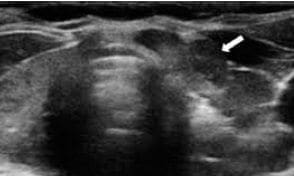

En el Hospital General de Castellón, la PAAF es practicada por los radiólogos, sea palpable o no palpable la lesión. Se selecciona el lugar más adecuado para la punción mediante ecografía o tomografía axial, se limpia la piel con una solución yodada y se aplica anestesia. La posición de la aguja es seguida por imagen, para evitar vasos sanguíneos y minimizar el riesgo de sangrado. Se utilizan agujas de 22G, que permiten obtener muestras tisulares pequeñas10,11 (figura 1).

Figura 1. Ecografía: la flecha señala el nódulo tiroideo.